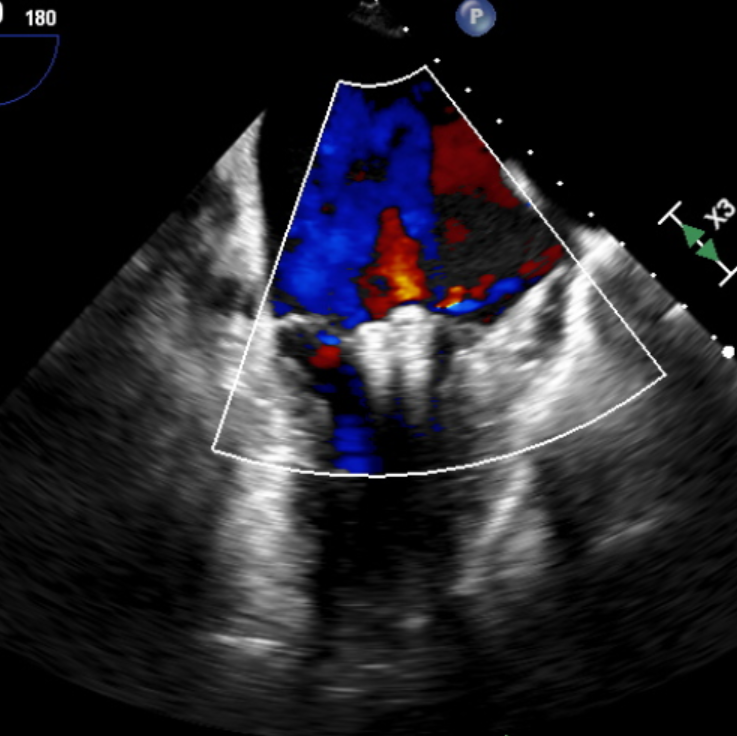

术后即刻TEE